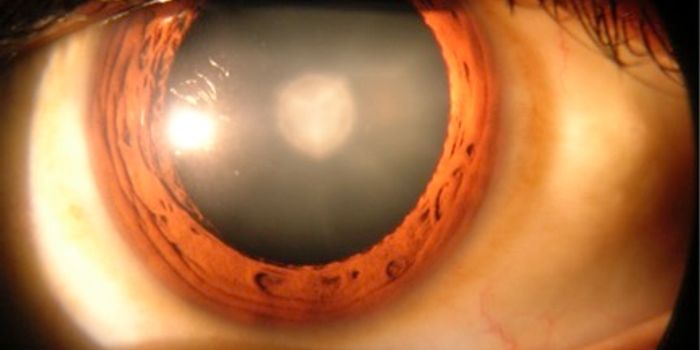

MAR 12, 2016Clinical & Molecular DXImagine seeing the world through a set of frosted glasses – this is what vision with cataracts looks like, blurry ...